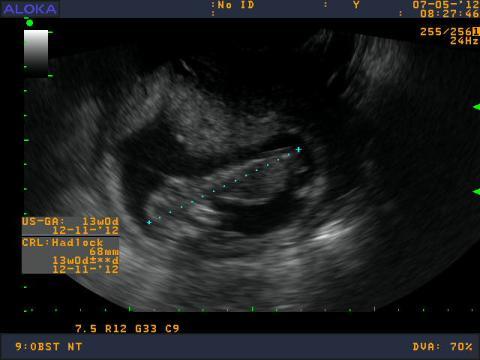

maminecka - 10.5.2012 6:44:16 Dobrý deň,chcela by som sa opytat. Gynekolog mi robil v 13tt vaginalne UTZ - meranie myslim ze sa vola CRL, lekar mi povedal, ze mam zle tkanivo na sonograf, že aby som sa neplašila, niektoré ženy ho maju dobre a niektoré zle, že to nemá vplyv na vyvoj dieťatka ale že malého nieje dobre vidno aj obrazok zo sona je nejasnejší oproti iným bábätkam v gestačnom tyždni 13tt, čiže meranie NT neprebehlo tak ako malo. Do materskej knižky mi napísal nepriaznivá poloha...prítomnosť nosoej kostičky tiež neviem. Vďaka tomu tkanivu, ale pri ukončení sona ma ubezpečil, že je to vitálna gravidita. Videla som špunta ako si tam v brušku robi kotrmelce a kopká. Ako mu bije srdiečko. Je pravda, že ked som bola 3 tyždne dozadu na UTZ srdiečko som lepšie videla ako teraz, dokonca vtedy som jasnejsie videla ručičky a nožičky. Musela som až oči prižmuriť. Možem to tkanivo nejako ovplyvniť? alebo jeto od prírody dané? a ešte otazočka. Mám sa znepokojovať ked nemám vobec to meranie NT vdaka tkanivu? este som zabudla babatko ma 68mm. Dakujem za odpoved. :-)

Dobrý den. S vlastnostmi vaší táně se nedá nic dělat. NT by ale zkušený gynekolog měl být schopen změřit vždycky (pokud to nejde přes břicho, měl by použít vaginální sondu).